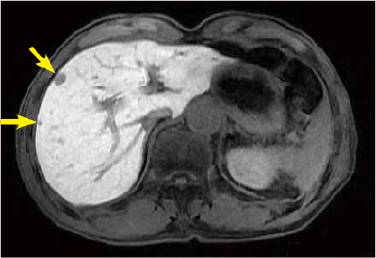

Fig. 3. EOB-MRI images

Two metastases less than 5 mm in diameter that could not be detected by PET-CT were found in S6 of the hepatic right lobe in the hepatobiliary phase of EOB-MRI. This nodule showed decreased diffusion in diffusion-weighted imaging.

Hepatobiliary phase

Diffusion-weighted image

(black-white inverted image)